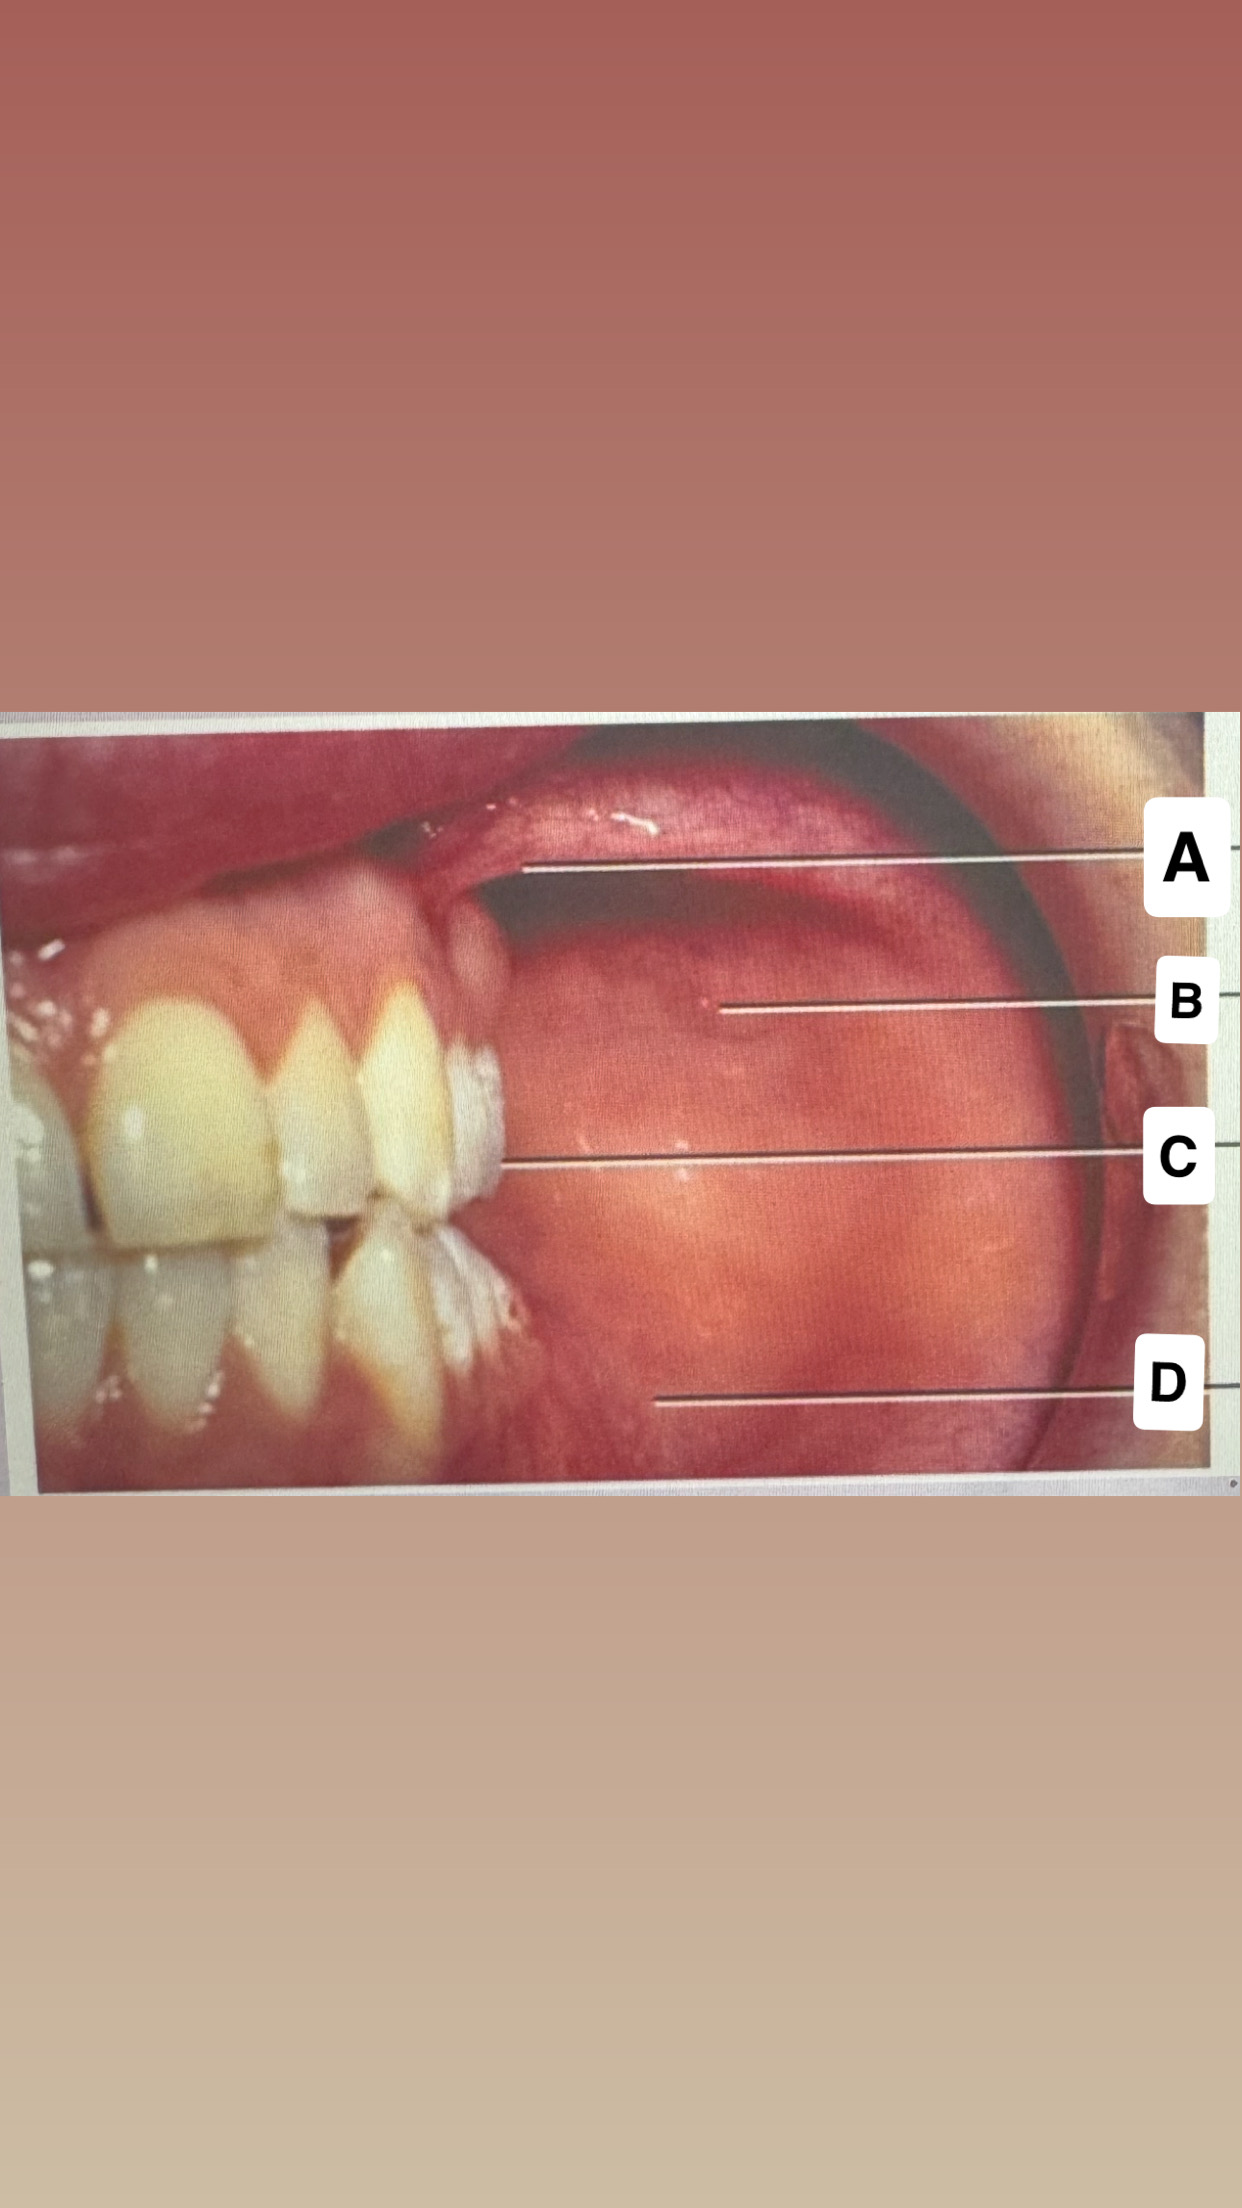

<p>Identify A</p>

Mucogingival

junction

<p>Identify B</p>

Alveolar

mucose

<p>Identify C</p>

Maxillary labial frenum

<p>Identify D</p>

Marginal gingiva